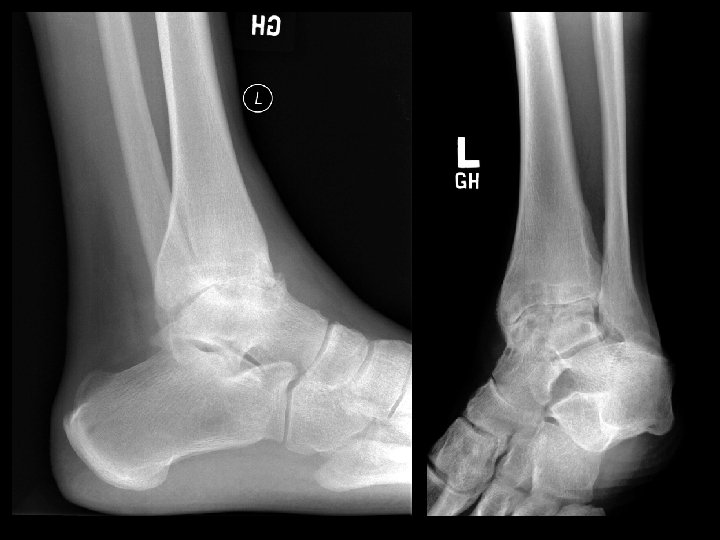

Hemophilia • Findings: – Severe secondary arthritis of the ankle • ddx: – Inflammatory – Post-infectious